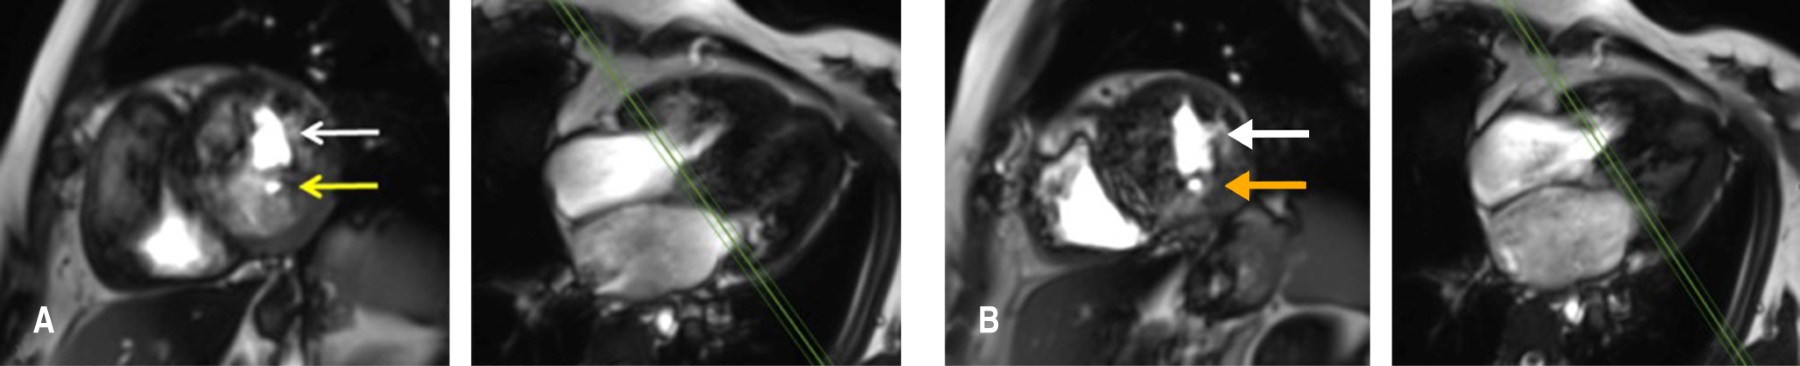

Las cardiopatías congénitas en México ocupan el segundo lugar de malformaciones congénitas en los recién nacidos, con una incidencia de 0.8-1.4%. El doble orificio de la válvula mitral (DOVM) es una cardiopatía congénita rara, con una incidencia reportada de 0.05%. Esta malformación consiste en la presentación anatómica de dos orificios mitrales comúnmente asociada a otras malformaciones congénitas como defectos septales, malformaciones completas o parciales del canal atrioventricular, coartación aórtica, tetralogía de Fallot, comunicación interauricular o interventricular, anomalía de Ebstein y persistencia del conducto arterioso. Las características clínicas son variables e incluso pueden pasar desapercibidas y ser diagnosticadas hasta la edad adulta. Se presenta el caso de una mujer joven el cual se encuentra asintomática con diagnóstico de hipertensión arterial, que durante una revisión de rutina fue diagnosticada con múltiples cardiopatías congénitas, de las cuales, su relación está poco descrita en la literatura, siendo este el tercer caso reportado. En la actualidad las técnicas de imagen multimodal permiten la mayor caracterización de las lesiones tanto de la valva como del aparato valvular, con la intención de realizar un abordaje diagnóstico y terapéutico integral para ofrecer el mayor beneficio al paciente.

Figura 4